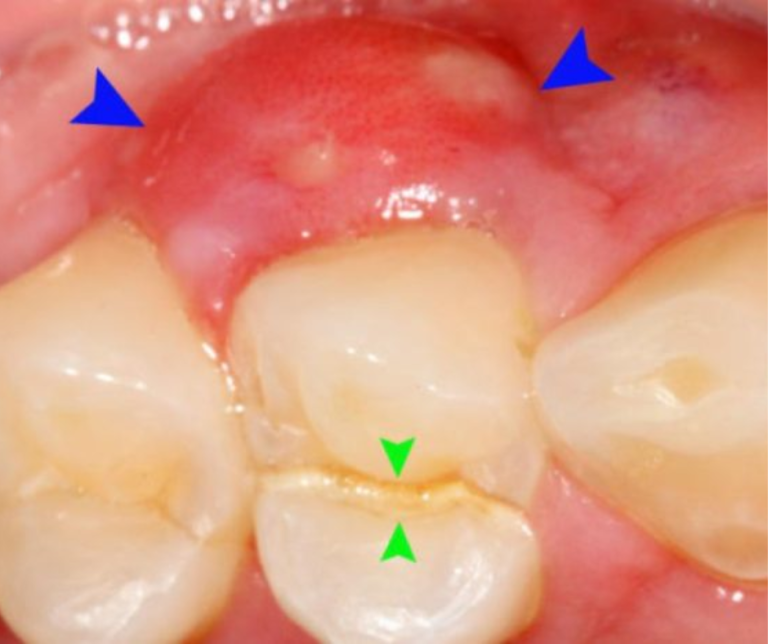

SƯNG CHÂN RĂNG HÀM DƯỚI VÀ CÁCH ĐIỀU TRỊ HIỆU QUẢ.

Sưng nướu răng hàm dưới hay viêm nướu răng là bệnh lý răng phổ biến nhiều người mắc. Sưng nướu răng hàm dưới do nhiều nguyên nhân gây nên. Việc sưng nướu lâu có thể...